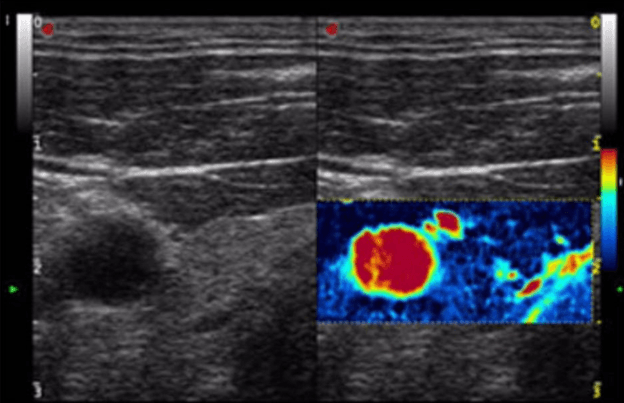

Tiroide ed ecografia tiroidea

La medicina specialistica in questione, oltre ai problemi legati al diabete, si occupa delle ghiandole endocrine che possono arrecare disturbi alla tiroide. Infatti, come si può leggere negli scritti di medicina specialistica della dottoressa Rosco, anche la tiroide è una ghiandola endocrina, la più grande del nostro organismo, e produce gli ormoni legati al metabolismo.

I problemi legati a una sua disfunzione possono essere evitati e curati all'interno del nostro studio, nel quale eseguiamo un'attenta ecografia della tiroide attraverso un meccanismo a ultrasuoni, sicuro e non invasivo.

Nuova tencologia per il rilevamento della microvascolarizzazione